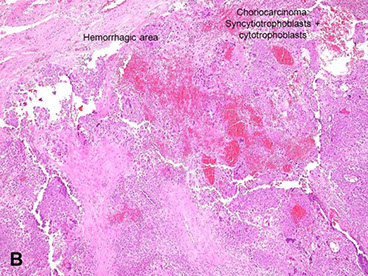

Choriocarcinoma

Gross: soft, fleshy hemorrhagic and necrotic, can be big or small

- sample the blood clot, especially at the periphery

Micro: Biphasic (all are cytokeratin and GATA3 +)

- cytotrophoblasts (CT, small, round mononucleated cells c clear cytoplasm) and intermediate trophoblasts (rIT, edder cytoplasm, has morphology of other 2 types??)

- syncytiotrophoblasts (ST, multinucleated) c variable atypia, pleomorphism, hyperchromasia, big nucleoli

- lots o mits, invades down to sm muscle and into vessels

- since doesn't make vessels, see lots of necrosis with only viable tumor found around periphery

- no villi are present

Choriocarcinoma, cytologic features

Choriocarcinoma can arise from within a placenta kind of as an in-situ lesion that looks like a white nodule; this is an example of an intraplacental choriocarcinoma in term non-molar placenta

Intraplacental choriocarcinoma in term non-molar placenta. See here how it is associated with the normal placenta